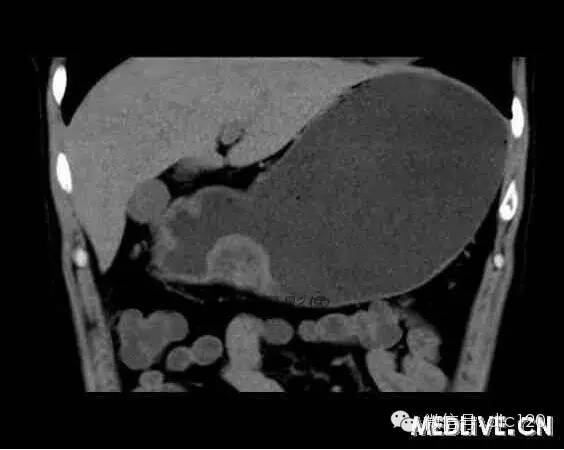

男,36歲,間斷性返酸噯氣3年,3個(gè)月前出現(xiàn)上腹疼痛,饑餓時(shí)加重。圖1-3為CT平掃,圖4-6分別為CT增強(qiáng)掃描的動(dòng)脈期、門脈期和延遲期。

CT檢查可見胃幽門前區(qū)胃小彎側(cè)胃壁局限性增厚、隆起或伴凸向胃腔內(nèi)的小結(jié)節(jié)灶,寬基地,境界光整,注射對(duì)比劑,增強(qiáng)掃描后,CT值可達(dá)50HU以上,與正常胰腺?gòu)?qiáng)化相仿。

胃迷走胰腺大多位在距幽門1-6cm的胃竇胃大彎側(cè),粘膜下層內(nèi),為1-3cm大小的病灶。 與胃壁以寬基底相,增強(qiáng)掃描病灶表面覆蓋的黏膜明顯強(qiáng)化且連續(xù),病灶內(nèi)無(wú)明顯壞死,病變強(qiáng)化方式類似于正常胰腺組織;當(dāng)病灶出現(xiàn)邊緣臍凹征或中央導(dǎo)管征時(shí),對(duì)EP的診斷具有一定的特異性。